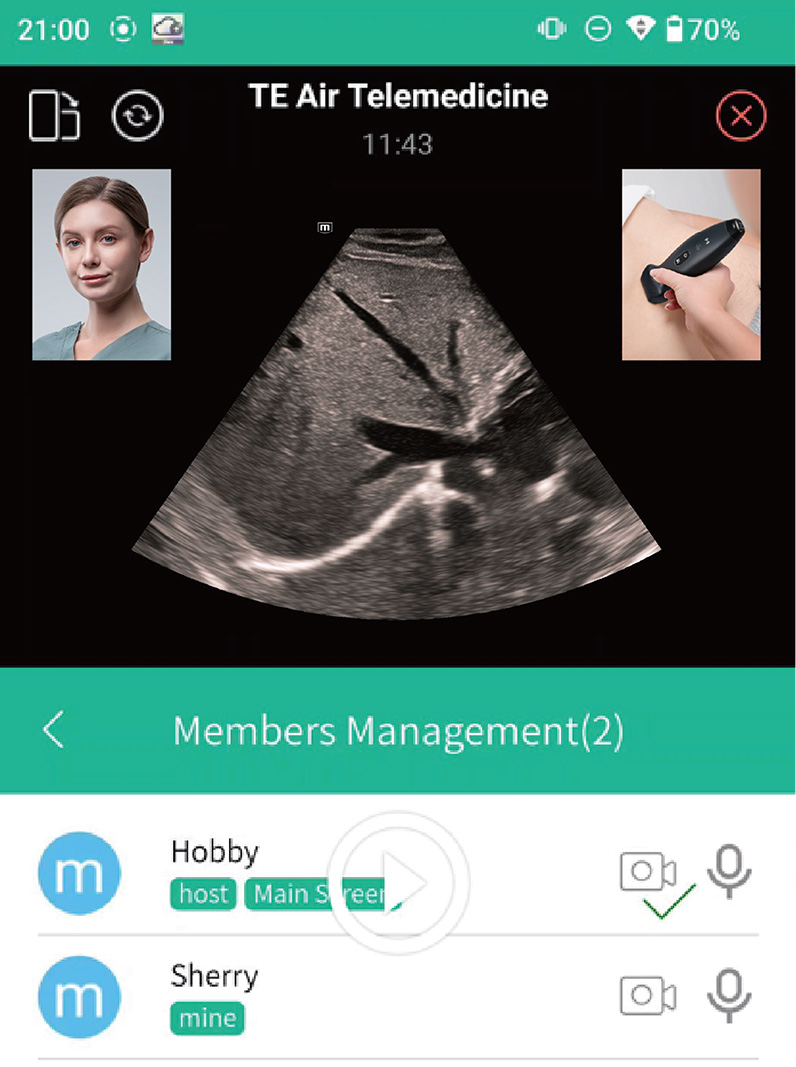

Integreert MiCo+ met de TE Air App om realtime delen van echografie?n, inclusief beelden, audio en video, naar het eindapparaat mogelijk te maken, voor begeleiding, training, kwaliteitscontrole, casusbesprekingen en meer